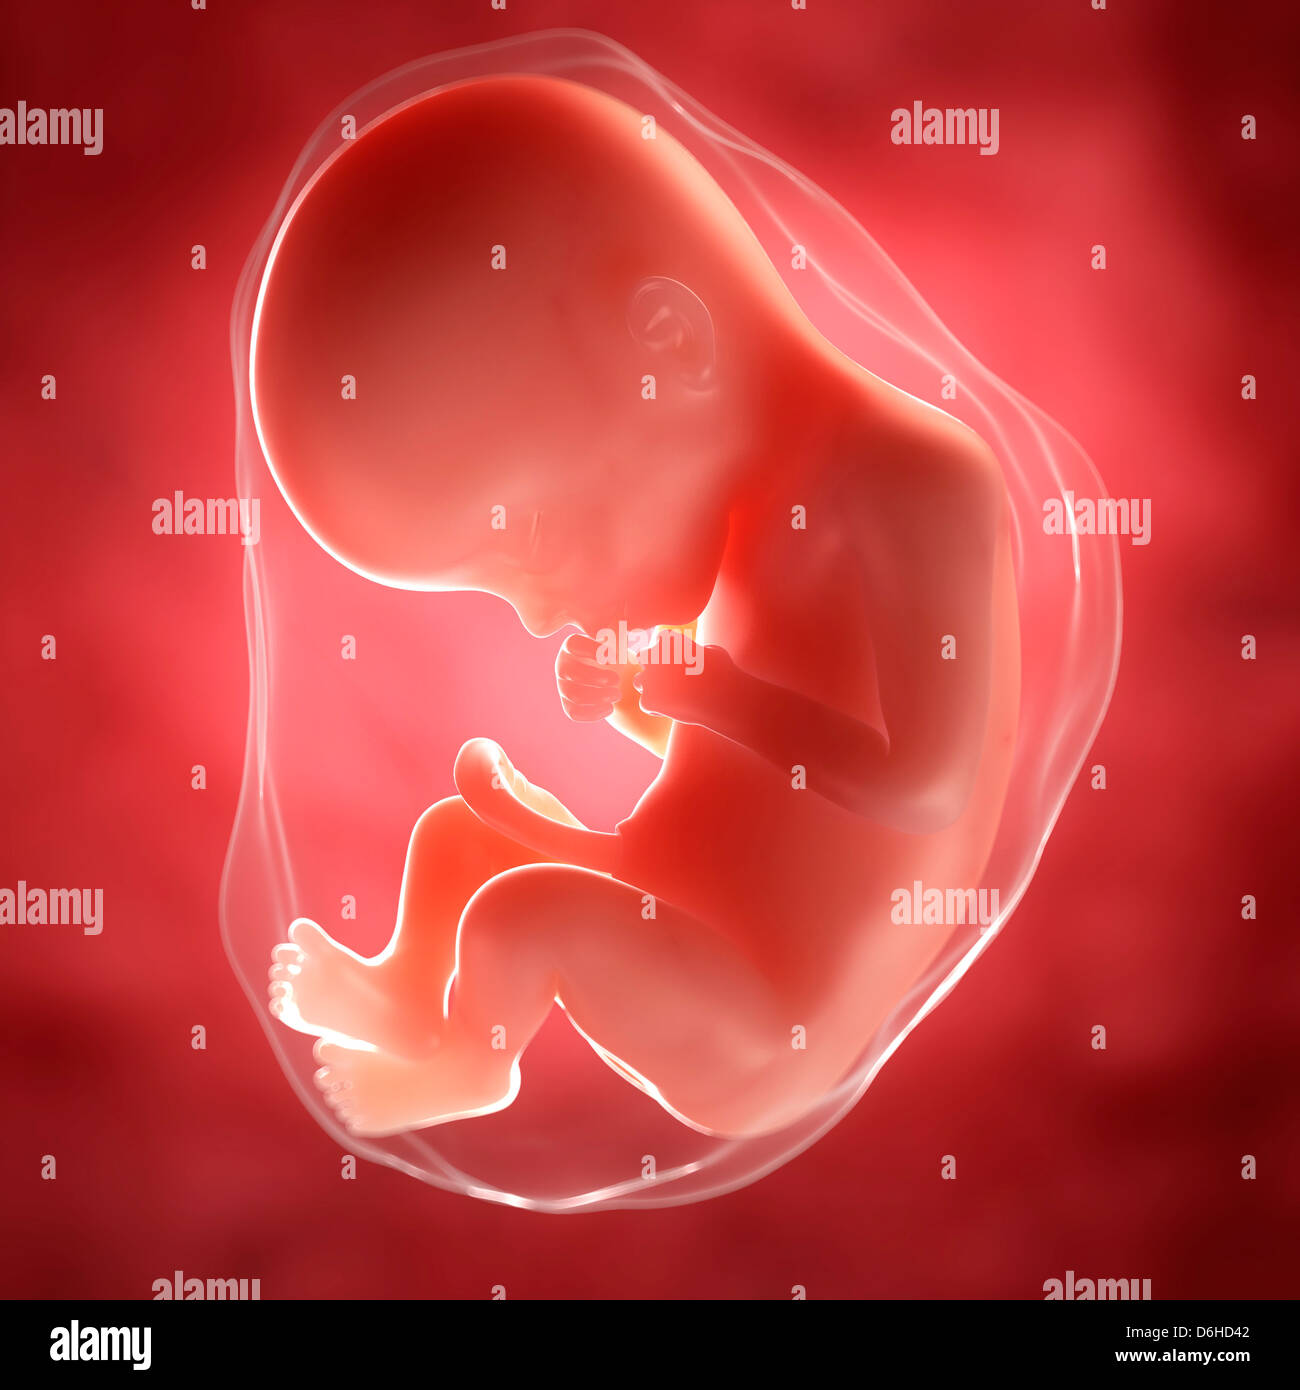

Feto A 22 Settimane Artwork Foto Stock Alamy

Feto Umano Eta 22 Settimane Illustrazione Foto Stock Alamy